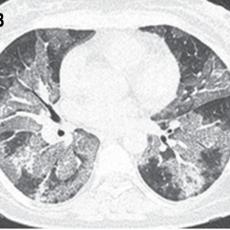

Escala tomográfica para evaluar la gravedad de COVID-19 en el Instituto Nacional de Enfermedades Respiratorias